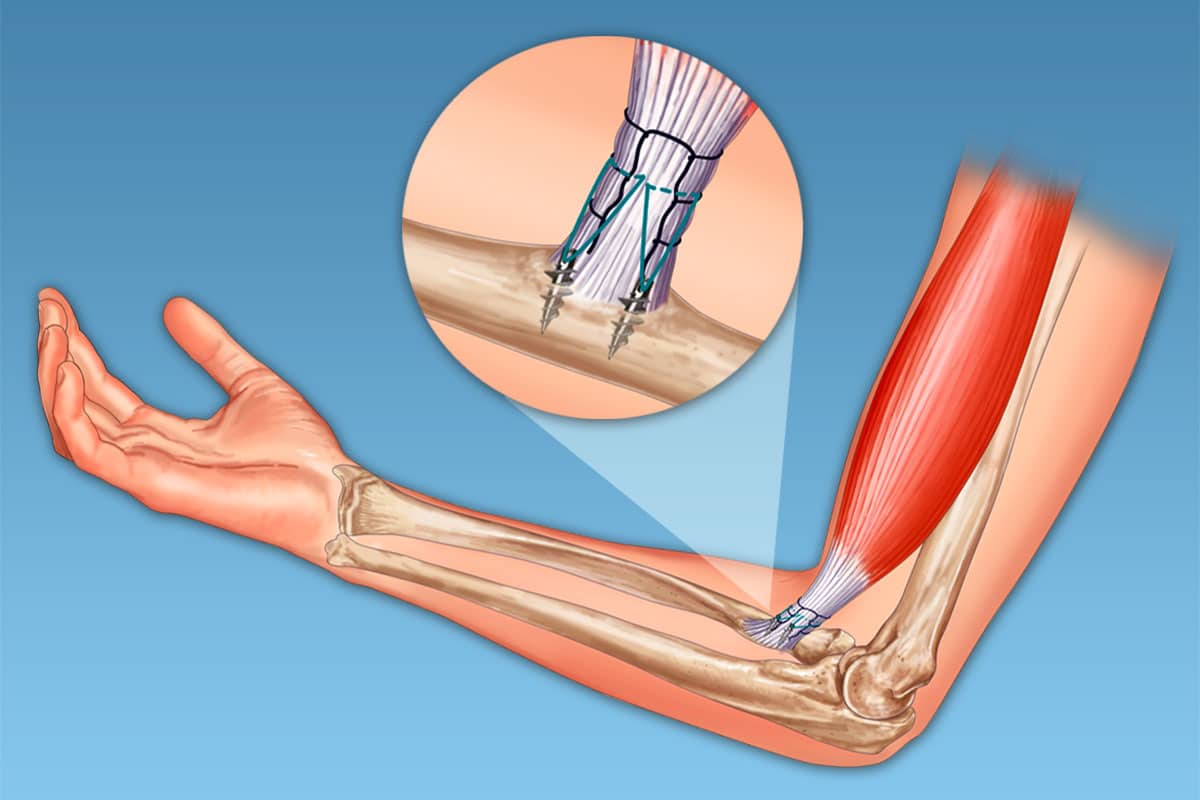

La rupture du biceps distal correspond à une déchirure complète du tendon qui fixe le biceps à l’avant-bras, au niveau du tubercule radial, près du coude.

L’opération permet une récupération quasi complète de la force et le retour au sport.